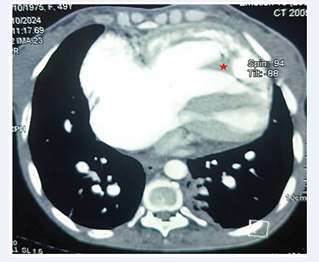

The patient was a 49-year-old housewife. The patient’s cardiovascular risk factors included a sedentary lifestyle. She presented with progressive onset, moderate-intensity pain in the left hypochondrium, associated with New York Health Association stage 2 dyspnoea, evolving in an apyretic context. Clinical examination revealed a blood pressure of 118/82 mmHg, an auscultatory arrhythmia with a heart rate of 108 beats per minute, palpatory pain in the left hypochondrium and a global heart failure syndrome. An emergency electrocardiogram revealed atrial fibrillation (AF). The chest X-ray showed significant cardiomegaly with major dilatation of the pulmonary artery and pulmonary hypervascularisation (Figure 1).

Figure 1 Front chest X-ray showing cardiomegaly, major dilatation of the pulmonary artery (red arrow) and pulmonary hypervascularisation

Figure 1: Front chest X-ray showing cardiomegaly, major dilatation of the pulmonary artery (red arrow) and pulmonary hypervascularisation